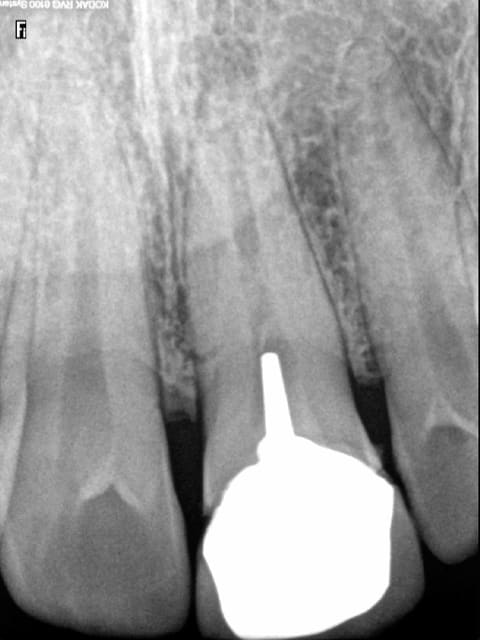

Ce qui est risible c'est que sur ces status contolés il y avait des endos pourries pour lesquelles les confrères responsables de ces merdes ne seront jamais inquiétés. Mais seules radios retenues comme valable par le CDC. -))))

Exemple ci dessous.